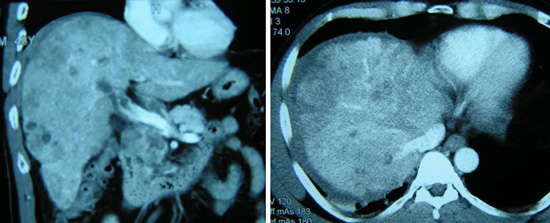

Sebuah PET-CT scan pada 23 Maret 2009 menunjukkan suatu kondisi kanker mulut rahim / cervix yang sudah lanjut dengan penyebaran ke arah rahim mencakup rahim dan bagian atas dari vagina. Terdapat pula banyak tanda-tanda adanya masa pada kelenjar getah bening yang tersebar didaerah sebelah kiri iliac, aorto-caval, recto-caval dan bilateral paraaortic , ini menggambarkan suatu penyebaran kanker ( metastasis ). Tidak terdapat tanda-tanda / bukti dari suatu metastasis didaerah peritoneal ataupun hati.

CT scan dibagian perut menunjukkan ada beberapa massa berukuran 7,3 x 5,1 cm ; 6,3 x 6,1 cm dan 7,3 x 4,5 cm, pada lobus kanan hati nya, dan diduga kanker hati yang telah menyebar atau metastasis kanker hati. Biopsi dilakukan pada tanggal 23 Desember 2010 dan dikonfirmasi sebagai kanker liver dengan sifat moderately differentiated.